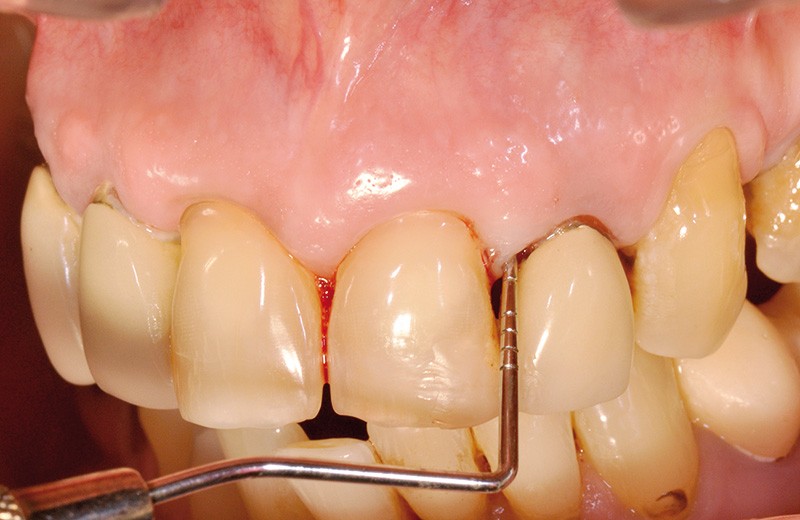

La réactivité clinique est la capacité d’un praticien à s’adapter et à envisager une solution thérapeutique. Cette séance, par son interactivité et par les différents cas cliniques exposés, va permettre aux praticiens de poursuivre leur enrichissement en situations cliniques. Ainsi, face à une fracture radiculaire (fig. 4a), la seule solution est-elle l’extraction ? Sur ce cliché (fig. 4b), la question est un peu provocatrice, et je vous engage à venir voir et écouter dans cette séance la solution apportée et surtout la pérennité de la décision choisie.